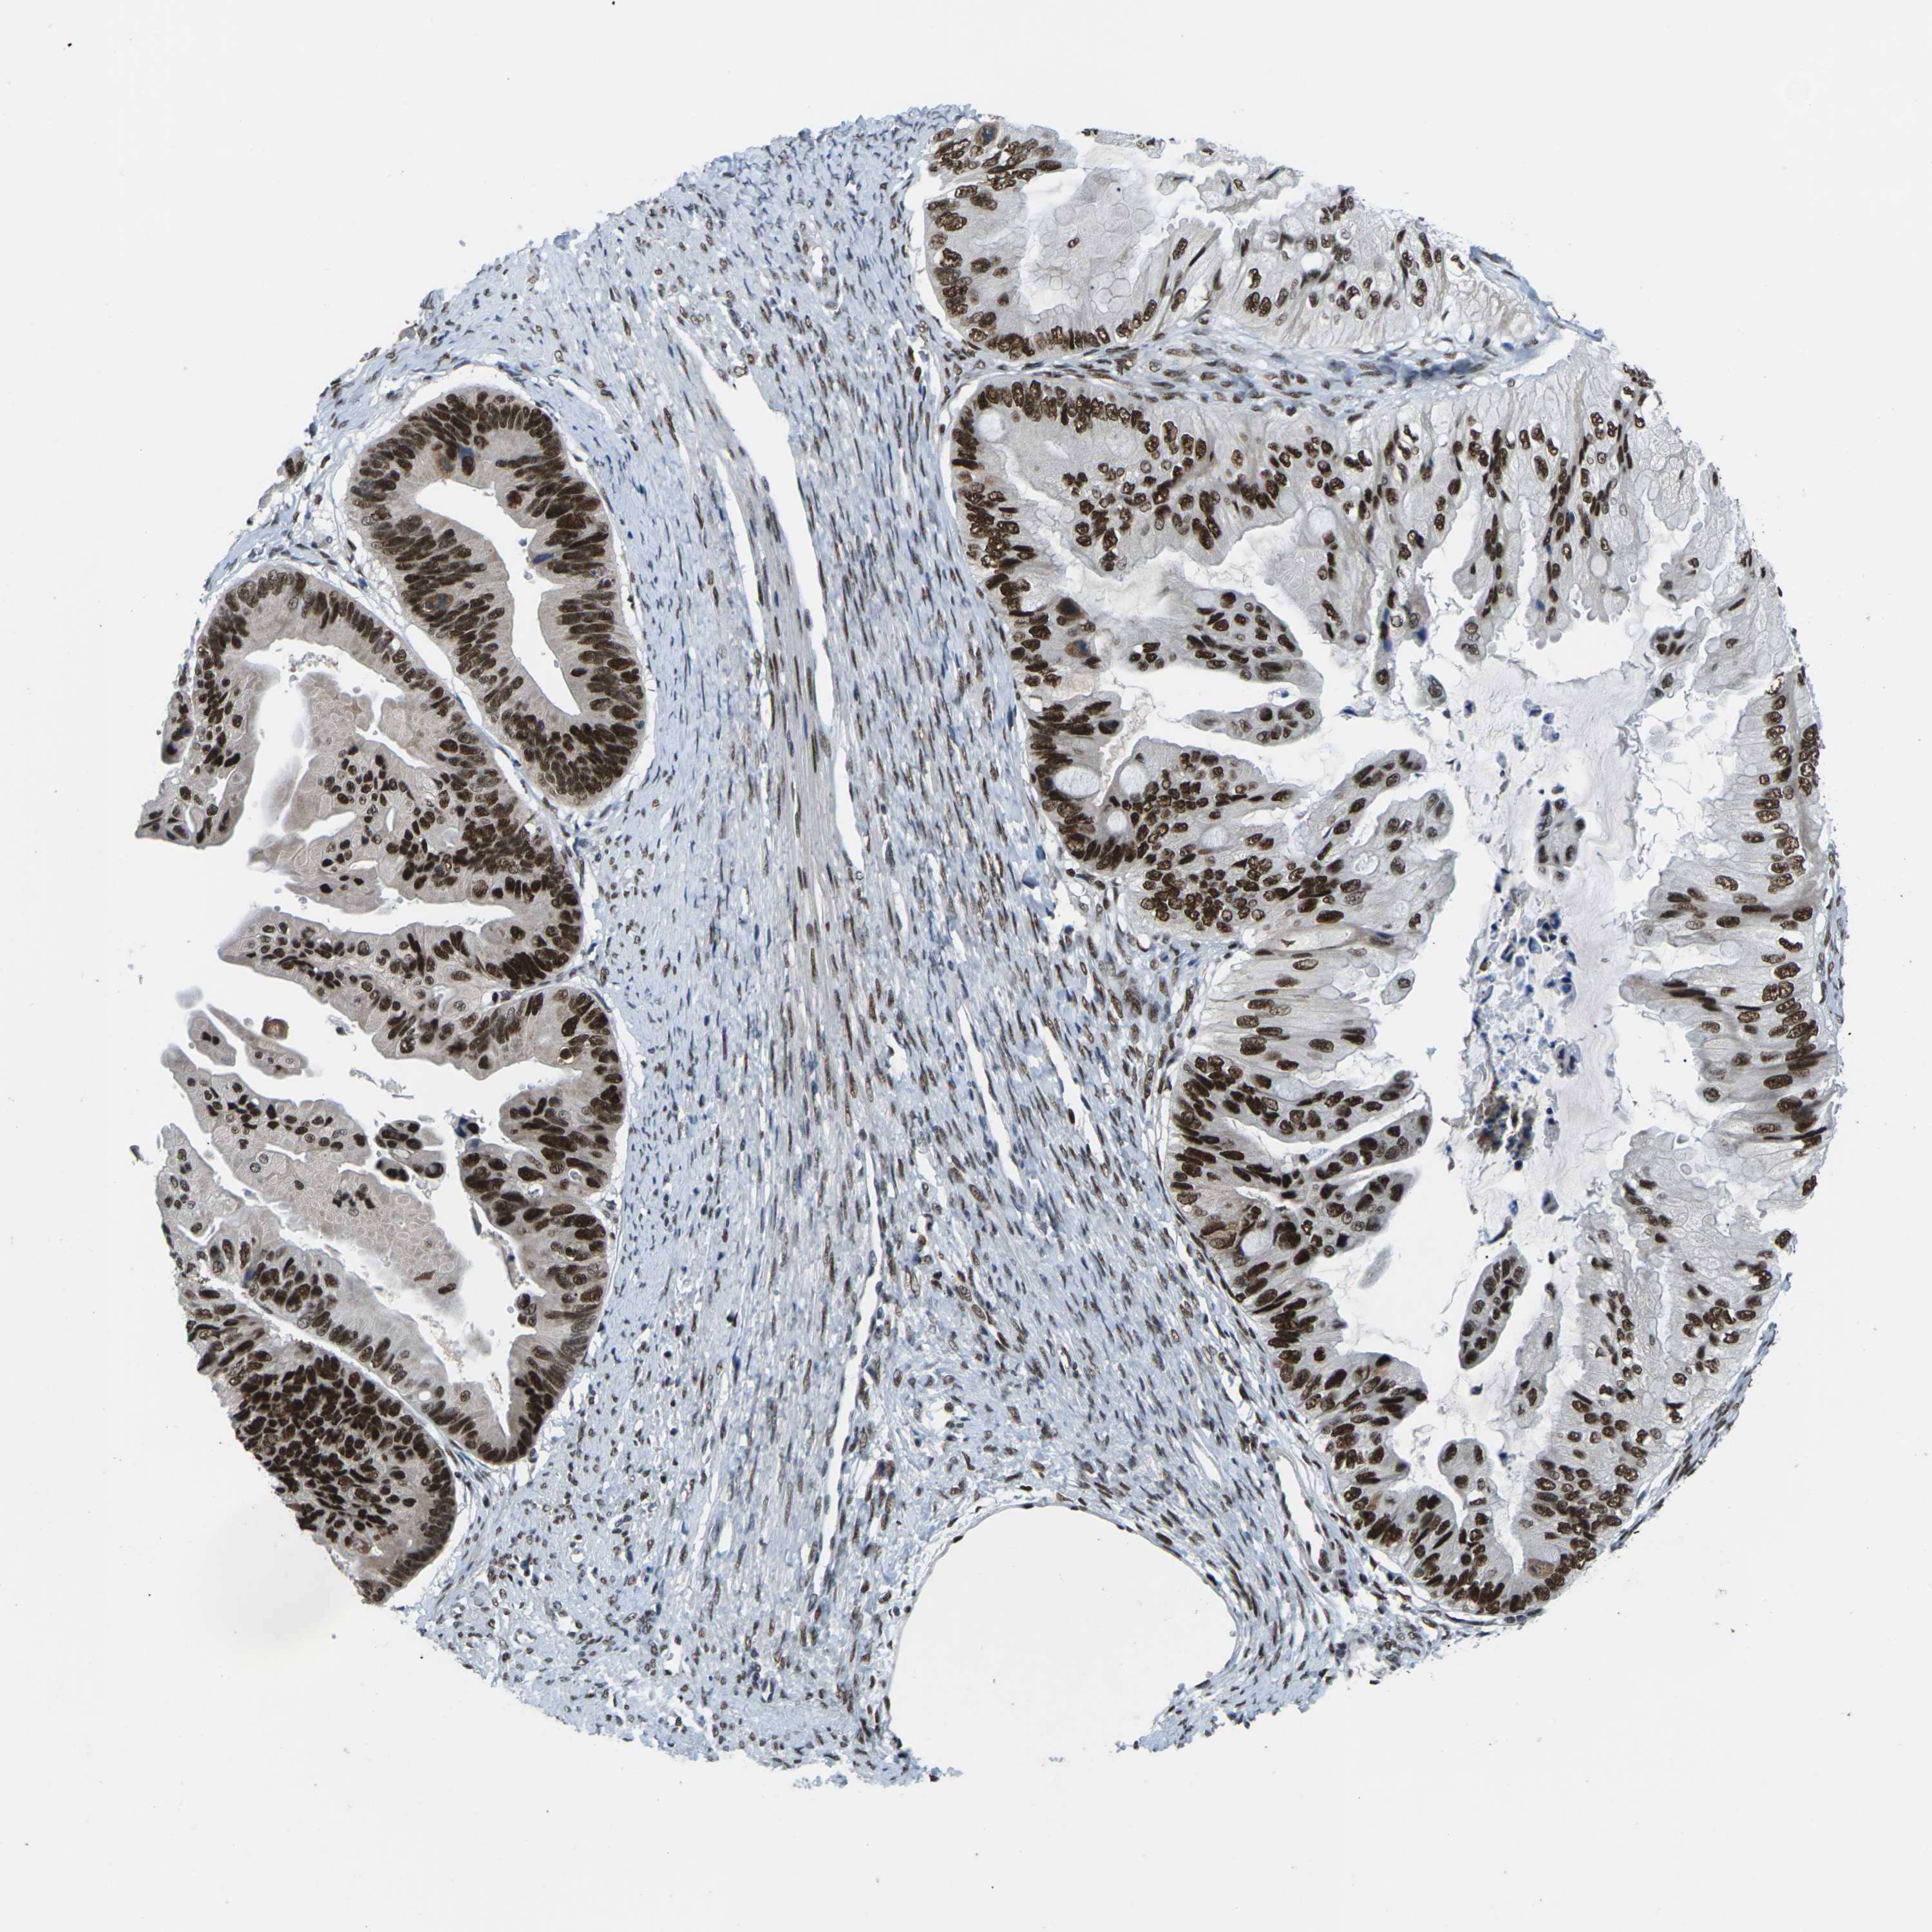

OVARIAN CANCER - Protein expressioni

A mouse-over function shows sample information and annotation data. Click on an image to view it in a full screen mode. Samples can be filtered based on level of antibody staining by selecting one or several of the following categories: high, medium, low and not detected. The assay and annotation is described here.

Note that samples used for immunohistochemistry by the Human Protein Atlas do not correspond to samples in the TCGA dataset.

Antibody stainingi

Antibody staining in the annotated cell types in the current human tissue is reported as not detected, low, medium, or high, based on conventional immunohistochemistry profiling in selected tissues. This score is based on the combination of the staining intensity and fraction of stained cells.

Each image is clickable and will lead to virtual microscopy that enables deeper exploration of all samples and also displays staining intensity scores, fraction scores and subcellular localization as well as patient and tissue information for each sample.

Antibody HPA012510

Antibody CAB008388

Staining

High

Medium

Low

Not detected

Intensity

Strong

Moderate

Weak

Negative

Quantity

>75%

75%-25%

<25%

None

Location

Nuclear

Cytoplasmic/membranous

Cytoplasmic/membranous,nuclear

Cystadenocarcinoma, serous, NOS

Carcinoma, endometroid

Cystadenocarcinoma, mucinous, NOS

Carcinoma, NOS